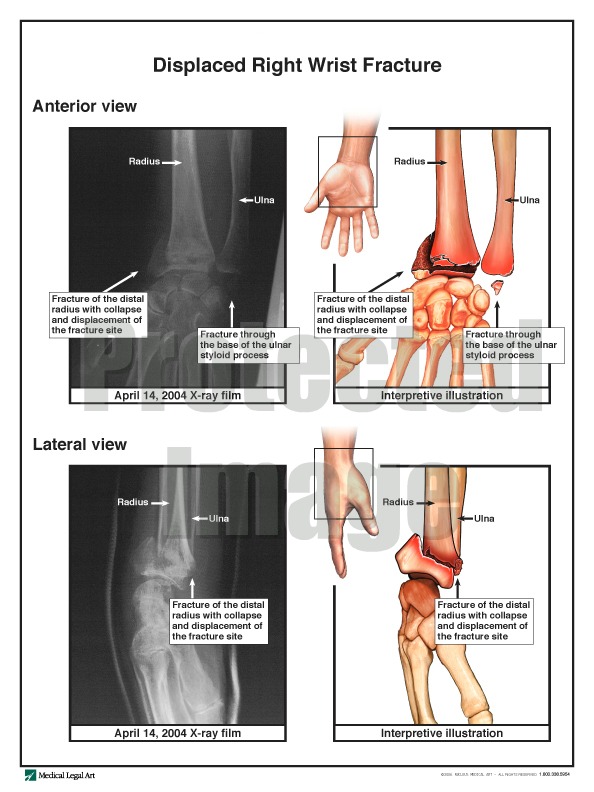

Impairment caused by the right wrist fracture caused her to have significant problems. Before the fall, the patient could ambulate, eat, position, and toilet herself without assistance. After the fall, she required assistance in all of these areas. Her injuries also prevented her from drinking enough fluids without assistance, as she had done before the injury. Yet, the nursing home consistently failed to provide the patient with enough liquids to drink, resulting in dehydration, a urinary tract infection, and an eight-day hospitalization. The patient was transferred to another nursing home when she was released from the hospital and died two years later of unrelaed medical problems. The jury returned a verdict for $1 million on claims for the nursing home’s negligence, fraud, and violations of the Virginia Consumer Protection Act.